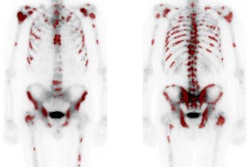

In a prospective study, Danish researchers found that only one patient among 81 subjects had a bone metastasis that was missed on a bone scintigraphy exam but detected on NaF-PET/CT. The modality also had no effect in predicting long-term patient outcomes, as it didn't discover any previously unseen bone metastases in patients who didn't respond to treatment.

In all, 75 patients (93%) achieved a biochemical response to treatment at the six-month follow-up, as confirmed by a prostate-specific antigen (PSA) level of less than 0.2 ng/mL. At 24 months after radical prostatectomy, no bone metastases were found in the one patient who showed a metastasis on initial NaF-PET/CT or in the seven patients who had equivocal results on the modality.